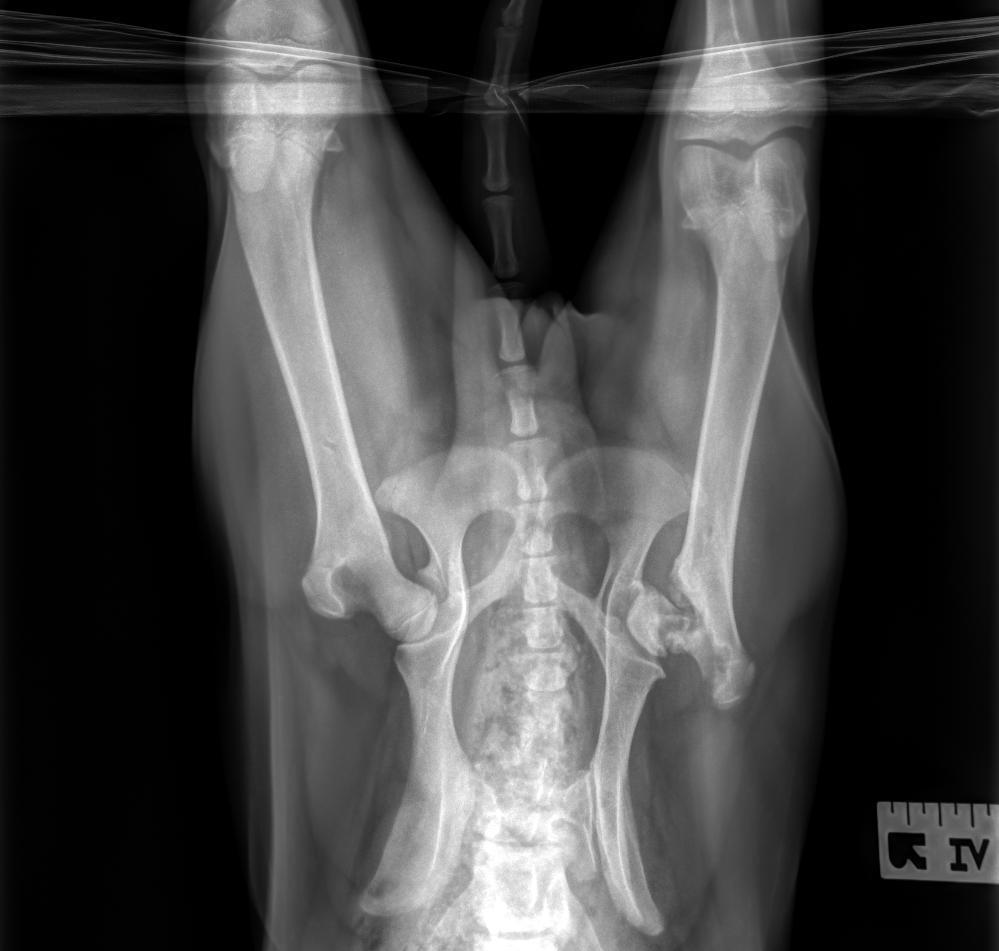

Just a baby, at 6 months old, Cocoa had lived more than 1/3 of her life on a cold shelter floor. You might call her lucky, to make a life saving trip and to land in a warm and loving foster home- but upon arrival, it was quickly discovered that something was terribly wrong. Cocoa's back leg bone, where it fits into her hip (femoral head) is not where it's supposed to be, and it's broken. She's been suffering with this debilitating pain, for no less than 2-1/2 months, likely longer. So maybe she IS lucky- we sure hope so- because with any luck, you will donate to help us raise enough money to cover the cost to have her painful, broken, baby leg- fixed! (more photos below)